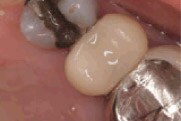

Figure 2

Tooth prep prior

to placement of Protemp™ Crown Temporization Material, buccal

view. |